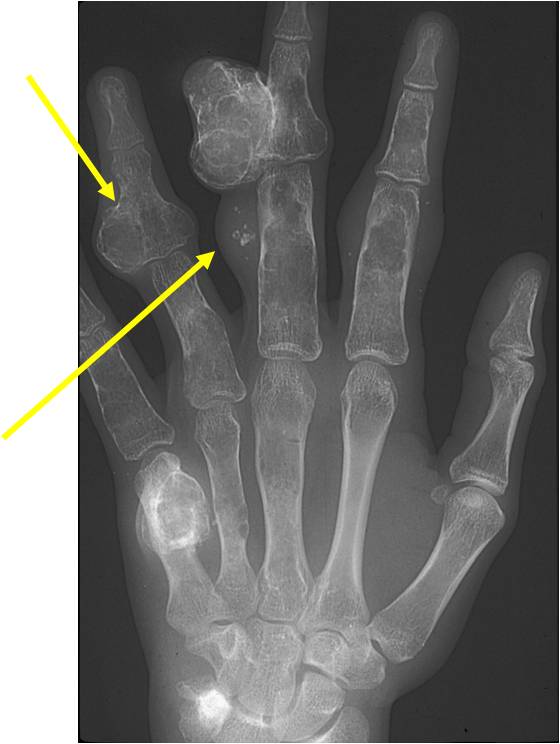

Maffucci Syndrome

- (Described in 1881 by Maffucci as enchondromatosis with hemangiomas)

Clinical Data:

- Very rare; Nonhereditary

- Multiple Enchondromas

- Cavernous Hemangiomas anywhere in skin and subcutaneous tissues of body

- May be unilateral or bilateral, may be only a few or many

- Phleboliths (calcifications) usually seen in hemangiomas on X-ray

- Mild male predilection

- Hands and feet greatest involvement

- Complications of hemangiomas

- Malignant Transformation: Chondrosarcoma (15-20%) Vascular Sarcoma (3-5%) Ovarian Malignancy Glioma and Carcinoma Unrelated to bone or soft tissue

Imaging characteristics:

- Lesions seen in infancy

- Typical enchondromas

- Geographic IA-IIB with expansion

- Lytic columns from epiphyseal plate

- Chondroid matrix calcification

- Growth disturbance and bowing

- Enchondroma growth slows after growth plate closure

- Maffucci: Soft tissue mass/hemangiomas with phleboliths

- Chondrosarcomatous transformation

- New bone destruction

- New periosteal reaction

- Disorganized or destroyed matrix calcification